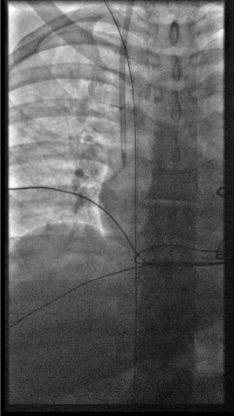

View final catheter position

Fluoroscopy showing tunneled dialysis catheter with tip in right atrium